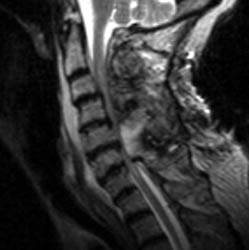

75 y.o. female with about a two-year history of continued gait abnormalities

and decreased dexterity. On examination her strength was normal, however, she

had bilateral Hoffmann signs as well as bilateral Babinski signs. Her strength

was 5/5 but her gait was ataxic. Magnetic resonance imaging showed severe

stenosis at C3, C5 and C6 levels. She underwent C3-C6 laminectomies.

Immediately post-operatively she did well, however, within 36 hours of the

operation, she slipped and fell due to spilled milk on the floor . After that

injury, the patient was neurologically intact. However, on postoperative day #2

for morning rounds, the patient was noted to be confused and weakened on the

left side, both arm and leg, leg more than the arm. An immediate CAT scan of the

brain and cervical spine was obtained. Immediate MRI was also obtained.

Non-enhanced sagittal T1 (A), sagittal T2 (B) and axial T1

images demonstrate a large fluid collection,

predominantly low signal on T1, bright on T2 with a few areas of T1 hyperintesity

mixed within. These constellation of findings are consistent with a

post-operative epidural hematoma with blood products of various ages. There is

severe severe spinal canal stenosis at C3-4, and very severe spinal canal

stenosis at C4-5 and C5-6. The cord is markedly flattened in the

anterior-posterior dimension, to approximately 2-3 mm secondary to mass effect

from this fluid collection. There is abnormal T2 weighted hyperintensity within

the substance of the cord at the C5-6 and C6-7 levels, consistent with some

edema.